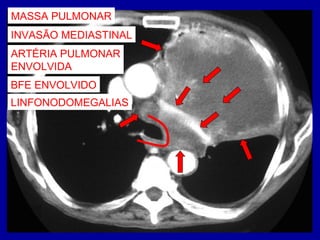

MASSA PULMONAR

MASSA?

LEMBRAR DE NEOPLASIA

QUAL MÉTODO DE IMAGEM

FAZER A SEGUIR?

TOMOGRAFIA COMPUTADORIZADA

NEOPLASIAS

RX = DIAGNÓSTICO

TC = ESTADIAMENTO

ESQUERDA

NEOPLASIA PULMONAR

EXTENSÃO PARA O

MEDIASTINO?

INVASÃO MEDIASTINAL

ARTÉRIA PULMONAR

ENVOLVIDA

BFE ENVOLVIDO

LINFONODOMEGALIAS